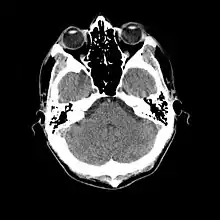

L'examen complémentaire essentiel à l'identification d'une méningite est l'analyse du liquide cérébrospinal obtenu par ponction lombaire[27]. Toutefois une telle ponction est contre-indiquée en cas de masse cérébrale (tumeur, abcès) ou d'hypertension intracrânienne, pouvant entraîner un engagement cérébral. En cas de situation à risque (traumatisme crânien, déficit immunitaire, signe neurologique focal, signe clinique d'hypertension intracrânienne), une imagerie cérébrale préalable est recommandée, avec un scanner ou une IRM[10],[26],[28]. C'est une situation concernant potentiellement environ 45 % des cas adultes[9]. Lorsqu'une imagerie est effectuée avant la ponction ou que celle-ci se montre difficile à réaliser, il est suggéré d'administrer un traitement antibiotique immédiatement afin de ne pas retarder le délai de mise en route du traitement[10], surtout si une telle attente est prévue pour dépasser 30 minutes[26],[28]. Souvent, lorsque l'imagerie n'est pas faite initialement, elle est faite plus tard dans les cas où il existe une complication[3].